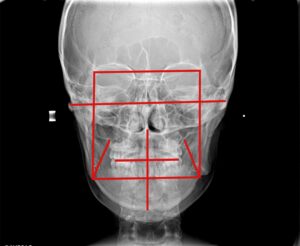

外科矯正治療後

理事長 萬 建一 歯科医師

歯学博士 / 一般社団法人日本歯科専門医機構認定 矯正歯科専門医 / 日本矯正歯科学会 認定医 / 日本成人矯正歯科学会 認定医・臨床指導医・総合指導医